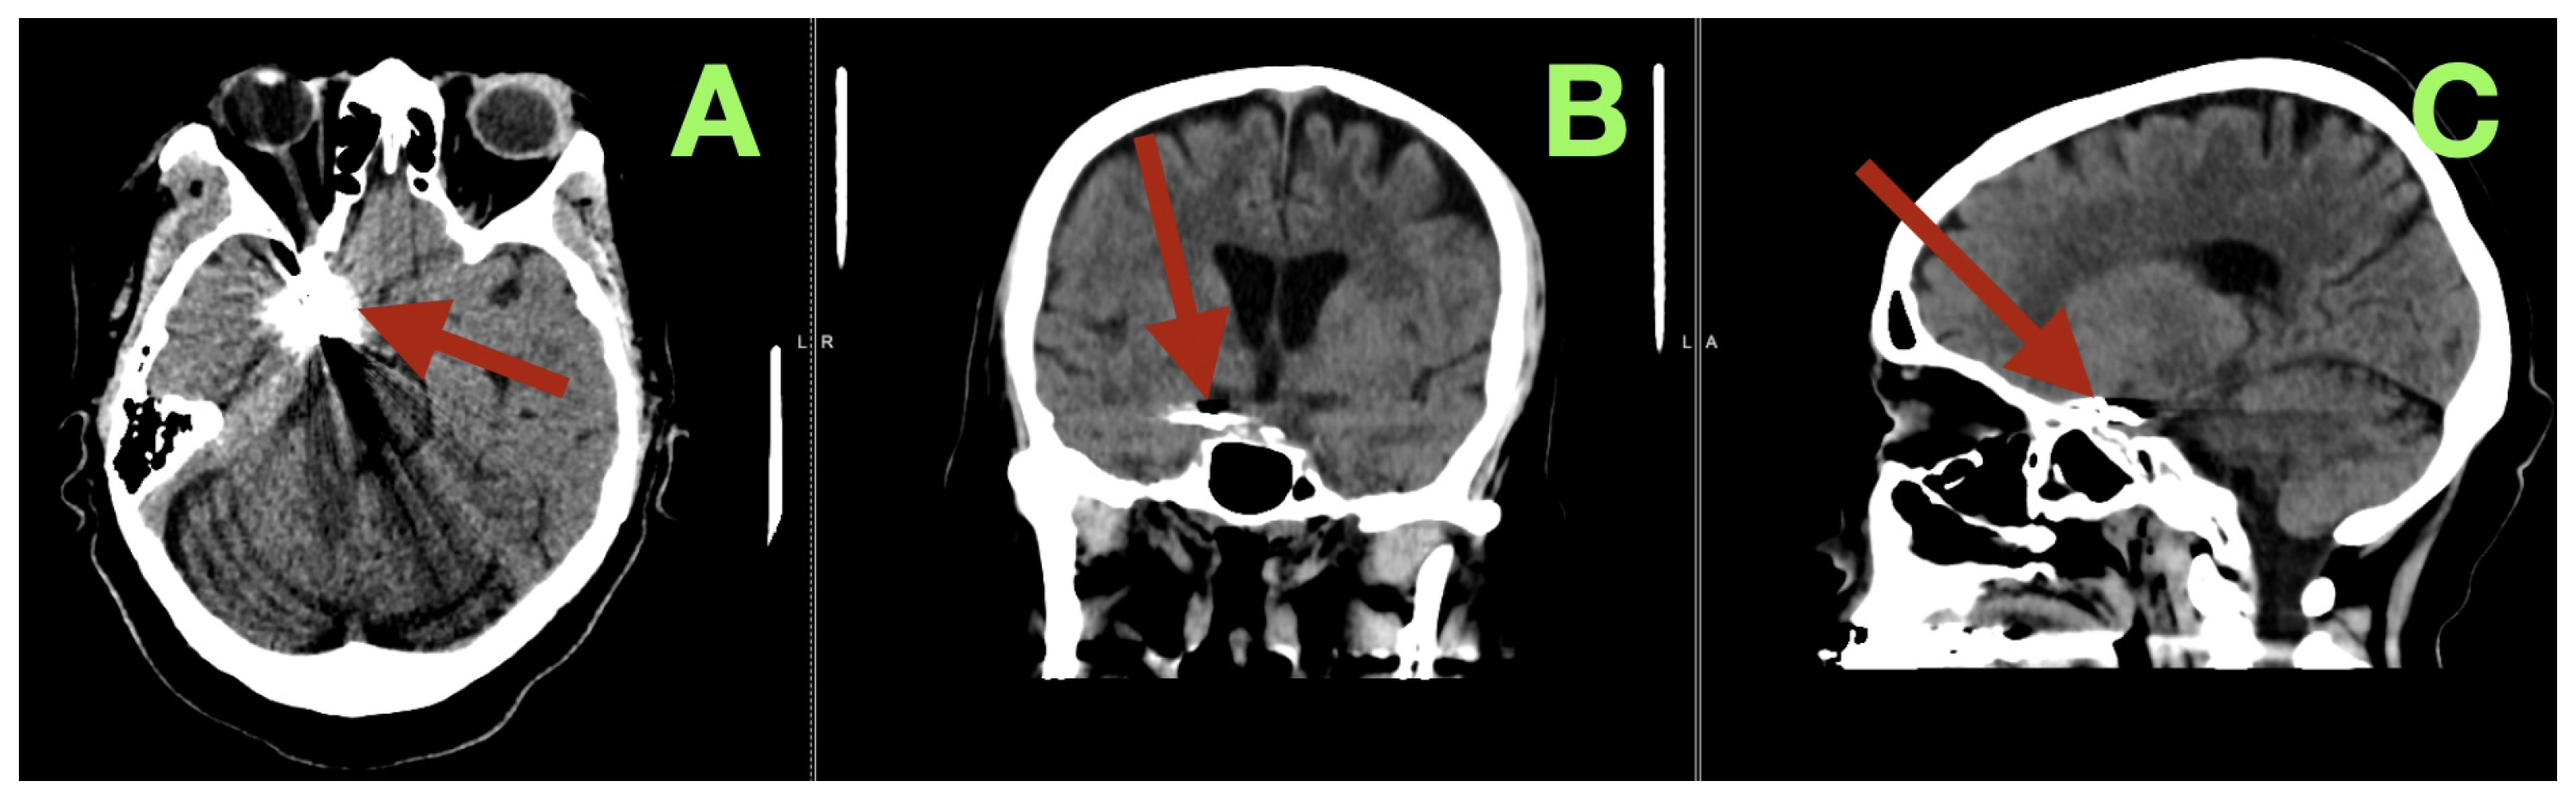

During the vasospasm-risk period, serial transcranial Doppler studies of the patient’s right middle cerebral artery (MCA) velocities ranged from 85 to 105 cm/s, and her fetal PCA (fPCA) velocities ranged from 55 to 70 cm/s, indicating that there was no clinically relevant vasospasm detected sonographically. On the fifth postoperative day, non-contrast CT (Figure 3) imaging confirmed the stable position of the clip, no interval hemorrhage, no territorial hypodensities, no interval change in the configuration of the ventricles, and no interval hydrocephalus. Additionally, the basal cisterns remained open, and the basal ganglia were normal in appearance.

Figure 3.

Postoperative day 5 non-contrast CT. (A) Axial section at the level of the skull base demonstrates the aneurysm clip at the right carotid–posterior communicating region (arrow), with expected localized metallic artifact and no evidence of recurrent subarachnoid hemorrhage, new intraparenchymal bleeding, or territorial hypodensity. The surrounding basal cisterns at this level remain discernible, without mass effect. (B) Coronal reconstruction confirms stable clip position within the right parasellar and suprasellar corridor (arrow), with preserved ventricular configuration and no radiographic signs of acute hydrocephalus or midline shift. (C) Sagittal reconstruction localizes the clip construct along the intended carotid–posterior communicating junctional plane (arrow), demonstrating anatomical coherence of the skull-base region and absence of secondary compressive changes.